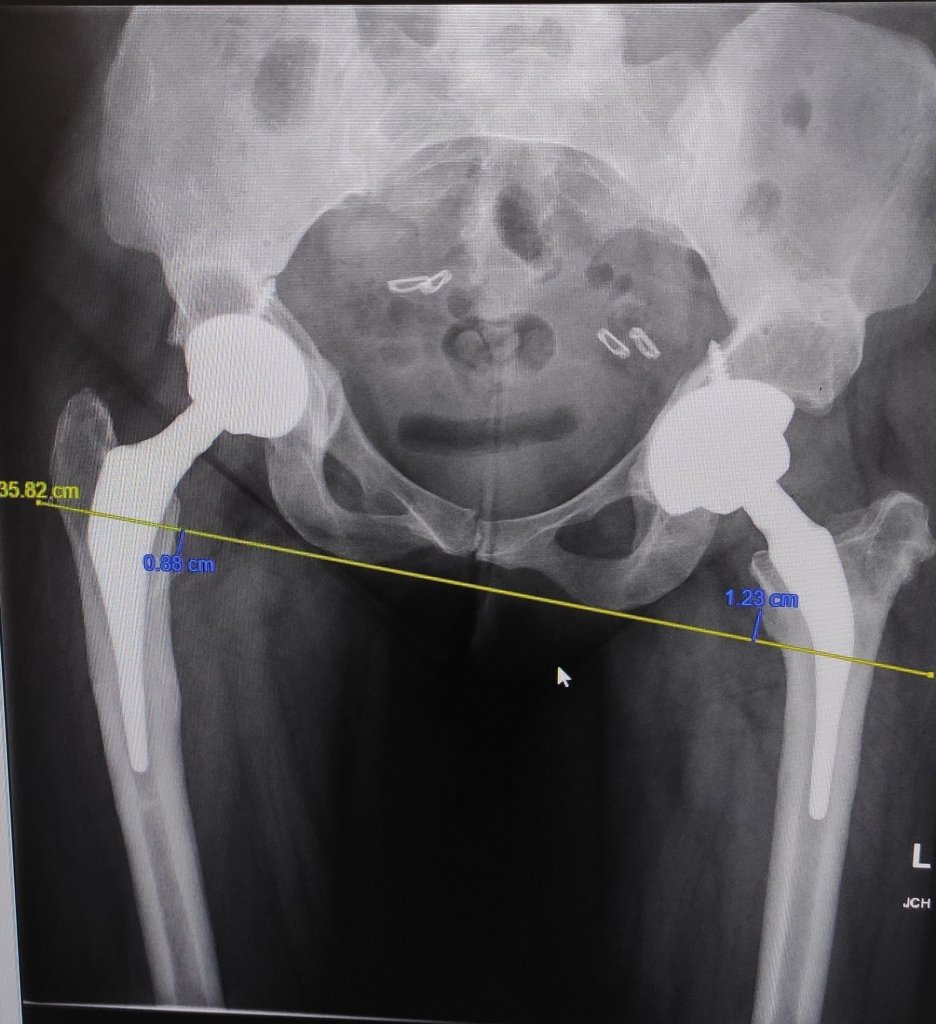

Once I got in, I was sent for an x-ray to make sure nothing is looking loose etc. I wear not metal on my lower half, so leggings.

And I’m in and out in mere minutes. And back to consultant. We had one of the most honest and open discussions, stating although I’m walking and it’s wonky, I fundamentally walk. And the state of the pelvis and spine, I am lucky I have that, and I am still pleased overall I had them replaced.

We’ve booked in the psoas, hopefully not a long wait. But in terms of tendon lengthening it’s not advisable as my tendons are too lax and it with be even weaker. The other options are usually try a smaller cup, but we did day of surgery and it kept dislocating. Or there is a revision but my age, my state of health bone wise that would be extreme.

So it’s a kinda I have to live with it, and accept it is getting inflamed and all I can do is physio and hydro to tighten it up, to lift it off the rubbing area, and never stop the physio, as it always comes back when I stop.